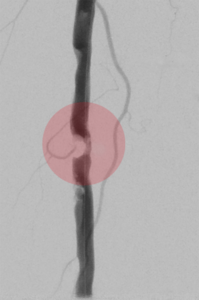

5. Thrombektomie – mechanische Entfernung von Blutgerinnseln

Wenn ein Gefäß durch Blutgerinnsel verschlossen ist, kann man den Verschluss mechanisch wiedereröffnen, indem man die Ablagerungen über spezielle Katheter absaugt. Dazu stehen uns Kathetersysteme, die mit Vakuum arbeiten bzw. zusätzlich die Gerinnsel vor dem Absaugen mit Hilfe von Wasserstrahlen oder Rotation der Katheterspitze zerkleinern, zur Verfügung.